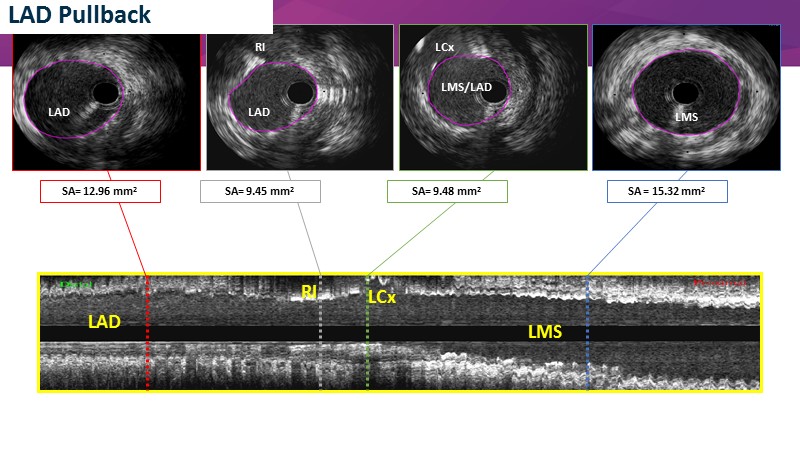

- To discuss contemporary treatment strategies for LMCA bifurcation lesions and to reflect on practical cases

- To explore state-of-the-art imaging on stent behaviour in bifurcation